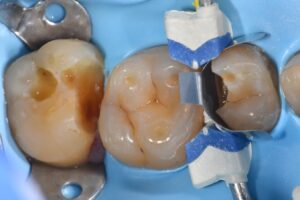

October 13, 2025 Direct Restoration #ClamplessDME #GarrisonCompositight #MajestyES2Universal Previous Post Next Post